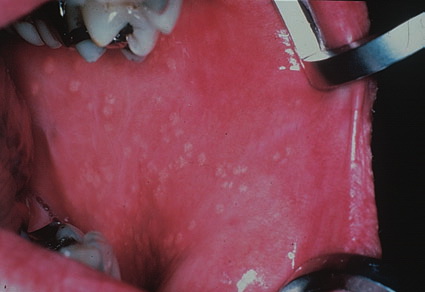

Fordyce spots

Fordyce spots are normal large, superficial sebaceous (oil-producing) glands seen on the moist tissue that lines some organs and body cavities (mucosal surfaces). The “spots” are asymptomatic and can be found on the head of the penis, the inner foreskin, and, most commonly, at the border of the lips. These sebaceous glands are not associated with hair follicles. These lesions are asymptomatic, but itching or irritation may occur if people treat the bumps inappropriately.